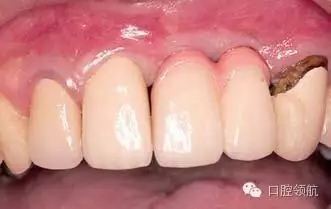

圖3 戴入有牙齦瓷的金屬基底烤瓷冠,(右上第3顆牙) 是不良修復(fù)體,計(jì)劃在(右上第1、2顆牙)種植區(qū)周圍的軟組織穩(wěn)定后,再對(duì)(右上第3顆牙) 進(jìn)行重新修復(fù)。

上述的患者具有較高的笑線,所以不影響美學(xué)效果(圖4、圖5)。近年,適合于牙齦色的瓷粉和聚合樹脂應(yīng)用于臨床,是較為可行的應(yīng)對(duì)方法。

圖4 上部修復(fù)體戴入口內(nèi)后,牙列和口唇的關(guān)系,由于笑線較高的原因沒有影響美學(xué)效果。